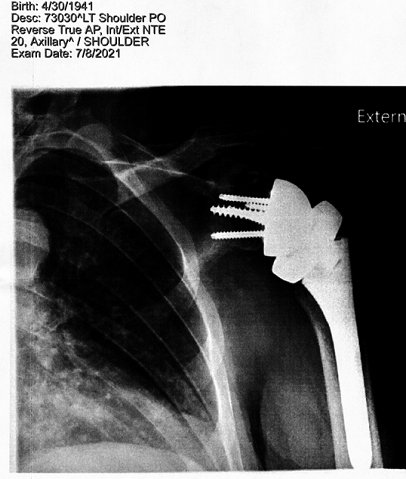

The surgery on

both

thumbs and 3 carpal tunnel surgeries have taken their toll on

the stamina in my hands and I am still recovering from a total

reverse shoulder

replacement.